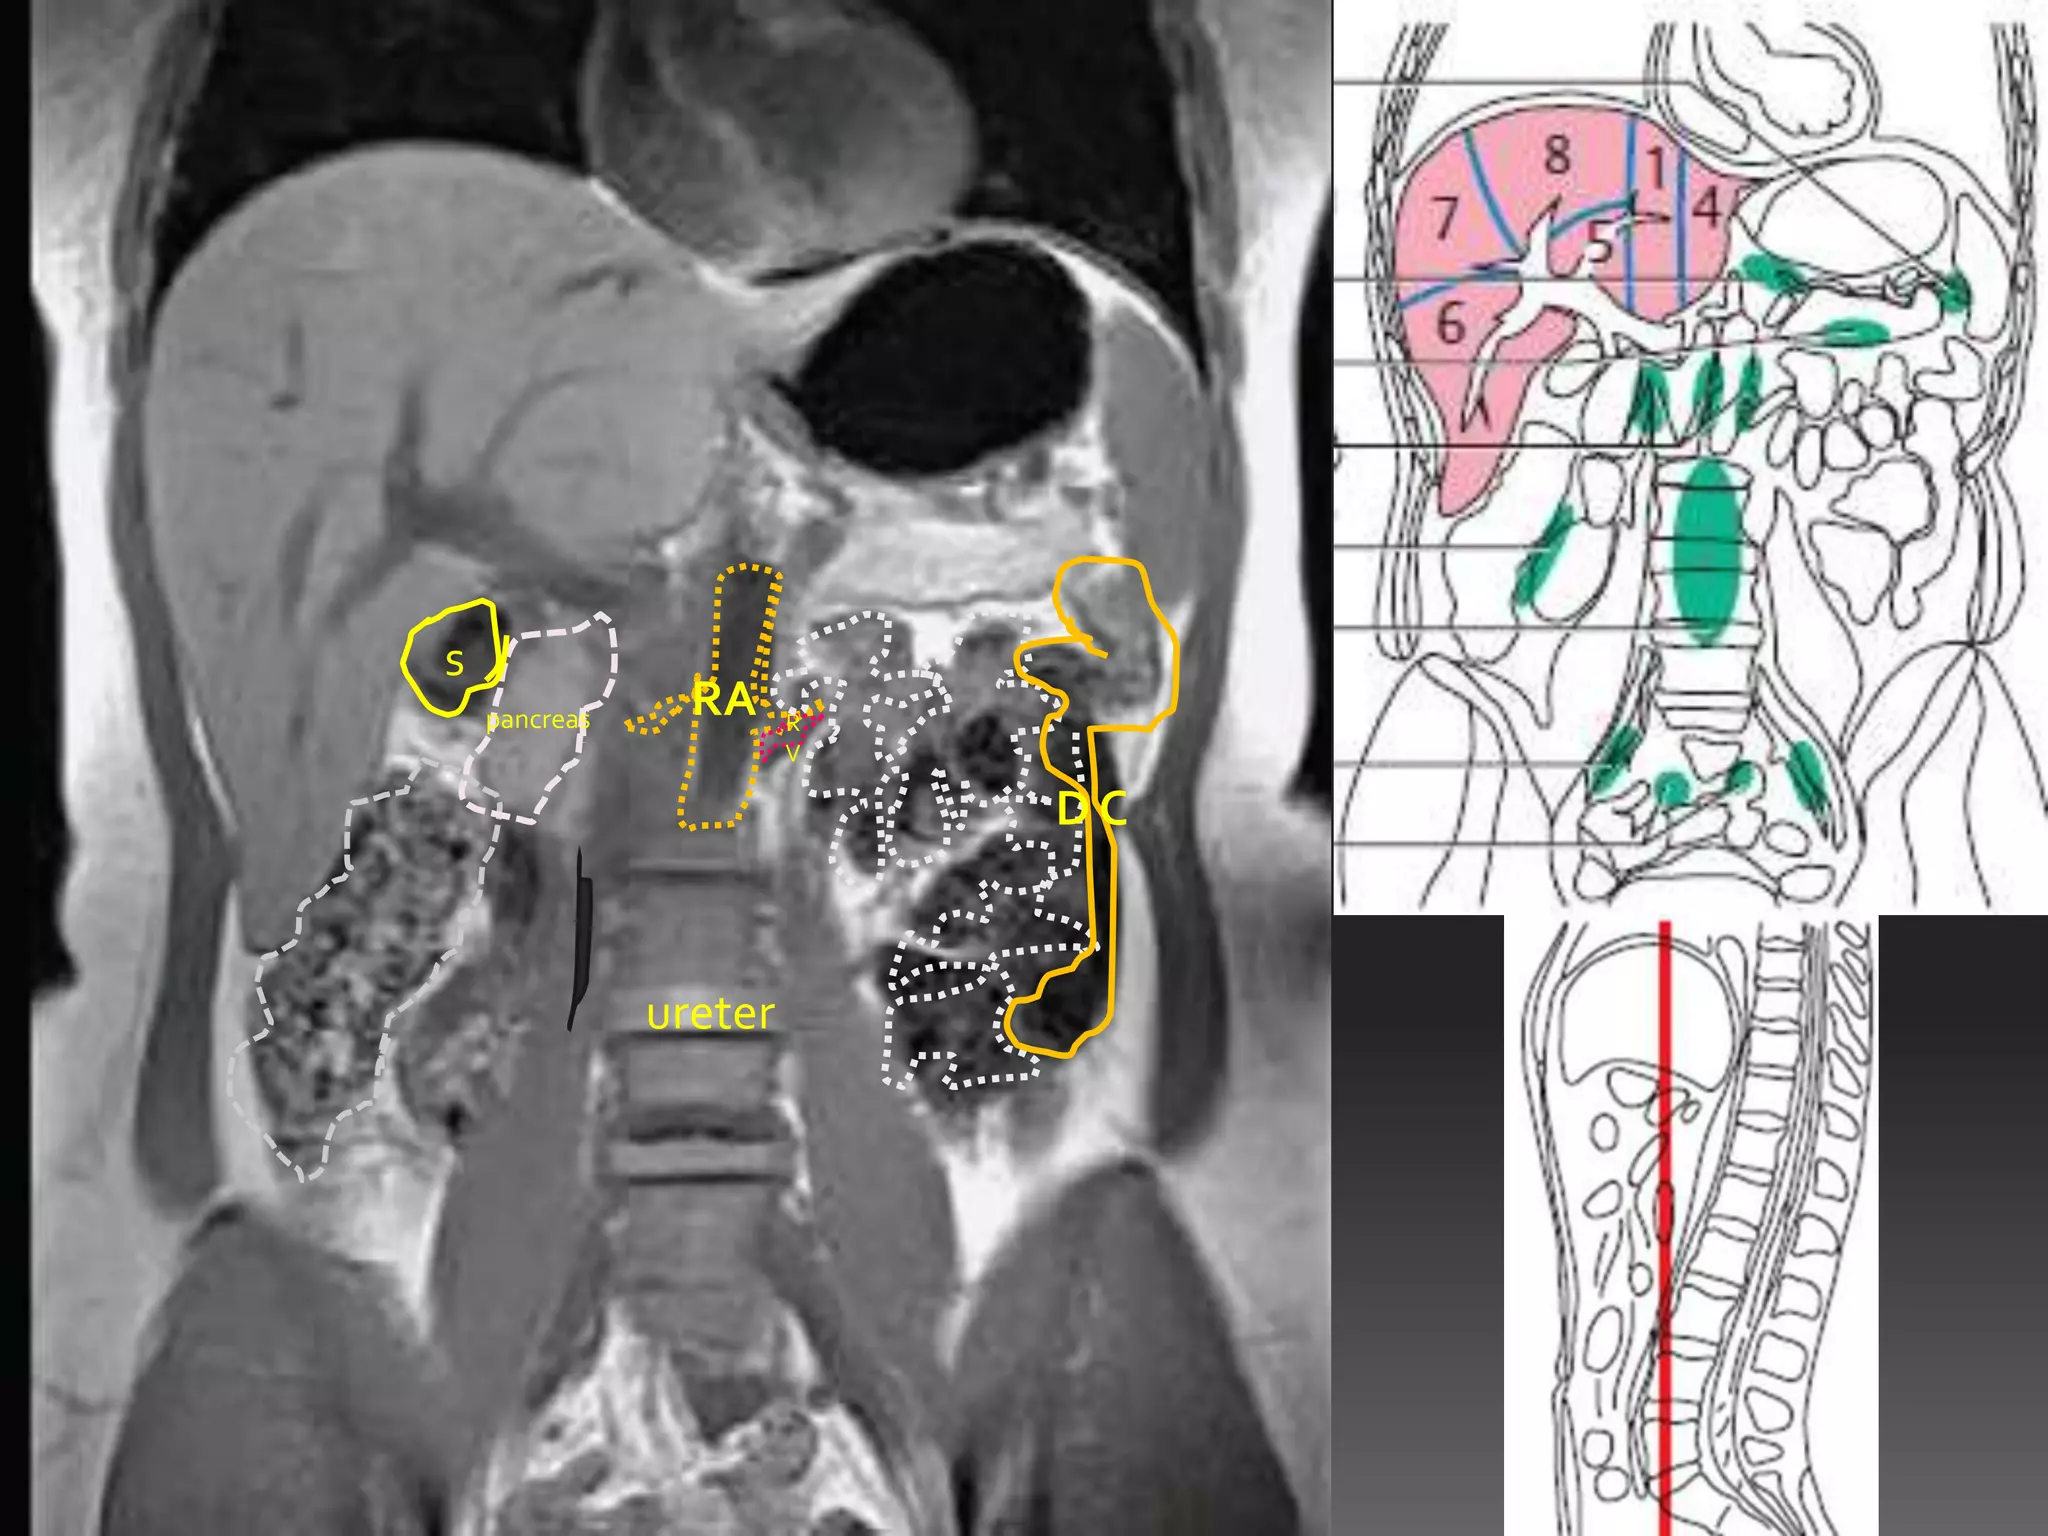

s

pancreas     RA     R

V

DC

ureter